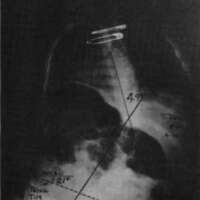

Let us now look at two examples were these stabilizing schemes have been simultaneously applied. Fig. 10a is a photo of a 12 year old boy with muscular dystrophy, sitting as he was presented to us. Fig. 10b shows the sitting support system properly applied. The corset is entirely independent; it is not attached to the seat. Fig. 10c and Fig. 10d compare his A-P spine x-rays without and with the orthotic system. The lateral tilt of his pelvis is reduced from 30 degrees to 14 degrees. The Cobb angle of his scoliosis was reduced from 65 degrees to 35 degrees. Curve control of this magnitude is not unusual as long as the deformity is still flexible. Fig. 11a is the x-ray of J.S., a 14 year old girl with cerebral palsy. She presented a right thoraco-lumbar scoliosis of 38 degrees and a rightward pelvic tilt of 8 degrees. Her shoulders were tilted 13 degrees to the left partly because she used her right arm for propping to avoid falling to the right. We provided her with a soft corset and the Gillette Sitting Support Orthosis. The Sitting Support Orthosis was to provide pelvic control and bilateral "propping" support. It had no head rest or anterior support. The x-ray taken just after fitting shows pelvic tilt reduced to 2 degrees (Fig. 11b), the Cobb angle of the scoliosis reduced to 22 degrees, and shoulders leveled. Both hands were free to function, and she said she could breathe deeper.

Figure 11a. X-ray of J.S., a 14 year old girl with cerebral palsy.

Figure 11b. J.S. provided with a soft corset and the Gillette Sitting Support Orthosis.